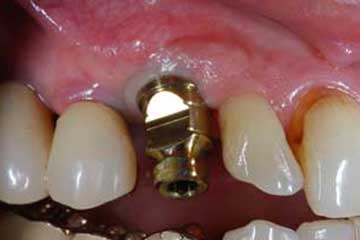

Impianto post-estrattivo

In un paziente cardiopatico di 72 anni